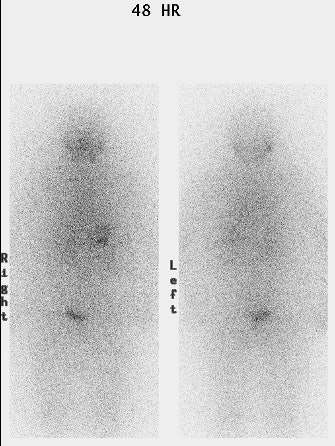

False negative I-123 diagnostic scan: The patient shown below had undergone thyroidectomy for papillary thyroid cancer and had a known metastasis to the left iliac bone. A diagnostic I-123 scan was performed to evaluate for extent of disease (posterior whole body image on left). The I-123 scan demonstrated neck bed uptake, but the iliac metastasis was not identified. Despite the negative diagnostic study, the patient received high dose I-131 therapy. The post therapy I-131 scan clearly revealed the iliac bone lesion (black arrow). |

|